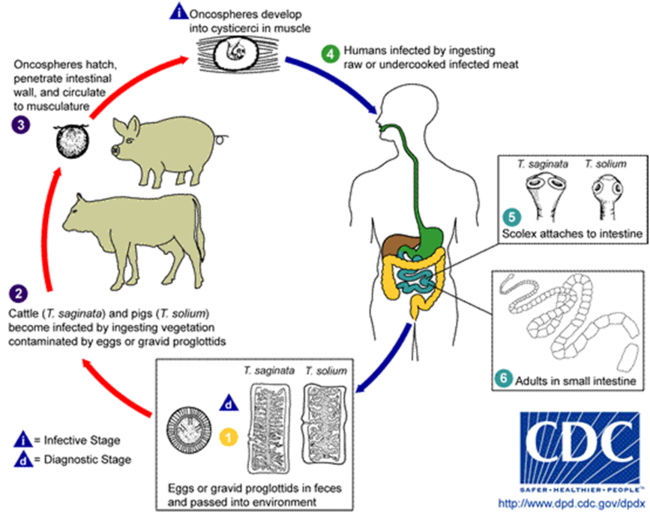

وتتميز الكيسة الخلوية بعدة ميزات تجعل الوقاية منها أسهل من البقرية وهي : • أنها كبيرة الحجم • كثيرة العدد • تتوضع في أماكن سهلة الرؤية كالنسيج تحت الجلد و تحت اللسان لدى الخنزير. طريقة انتقال الخمج : 1- داء الشريطية المسلحة المعوي : تكون الكيسة المذنبة الخلوية هي الطور الخامج , وينتقل الخمج للإنسان عن طريق تناول لحم الخنزير النيئ أو غير المطهي جيداً أو المدخن الحاوي على الكيسة المذنبة الخلوية . 2- داء الكيسات المذنبة وهو خطير بالنسبة للمصاب و بالنسبة للمخالطين له : تكون البيضة هنا هي الطور الخامج , ويصاب الإنسان به بإحدى الطرق التالية : - ابتلاع الطعام و الماء الملوث بالبيوض . - إنتقال البيوض بطريق : شرج – يد – فم عن طريق الأيدي الملوثة بالبيوض وهو أكثر الطرق شيوعاً (خمج ذاتي خارجي) . - بالحركات الحوية العكوسة التي تدفع بالقطع أو بالبيوض نحو العفج فتفقس و يتحرر منها الجنين مسدس الأشواك (خمج ذاتي داخلي ) .

دورة الحياة :

داء الشريطيات المعوي :

تنفصل القطع الأخيرة من الدودة بشكل مجموعات تتألف من 5 – 10 قطع غير متحركة وهي تخرج مع البراز . وتتابع دورة حياة كالشريطية العزلاء إلا أن ثويها المتوسط هنا هو الخنزير حيث تتشكل فيه الكيسة المذنبة الخلوية التي تتوضع خاصة في عضلات رقبته وكتفه و قلبه و في النسيج تحت الجلد و تحت اللسان .

داء الكيسات المذنبة عند الإنسان :

لدى وصول البيوض إلى العفج ينحل غلافها و يخرج الجنين مسدس الأشواك الذي يخترق جدار الأمعاء ويدخل الأوعية ليصل إلى النسج و تحتاج الكيسة لمدة شهرين تقريباً ليكتمل تطورها وهي تتوضع مرتبة حسب كثرة حدوثها في : 1- النسيج الضام تحت الجلد 2- العين 3- الدماغ 4- العضلات الارادية 5- القلب 6- الكبد 7- الرئتين ولكن أخطرها هو التوضع العصبي و التوضع العيني